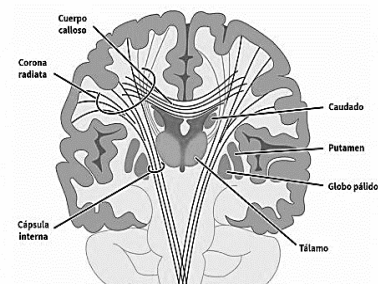

Doença grave, neurodegenerativa e progressiva com

transmissão autossômica dominante. A clínica

apresentada na doença inclui movimentos coréicos, constituindo a alteração motora mais frequente, além de

distúrbios de comportamento caracterizados por

irritabilidade, insônia, ou sintomas depressivos e

alterações na memória. A fisioterapia parece ser um

tratamento útil em qualquer fase da doença. A imagem

que segue revela, em corte frontal, possíveis estruturas

comprometidas neste caso. Escolha a opção correta com

o diagnóstico e regiões comprometidas para essa

doença.